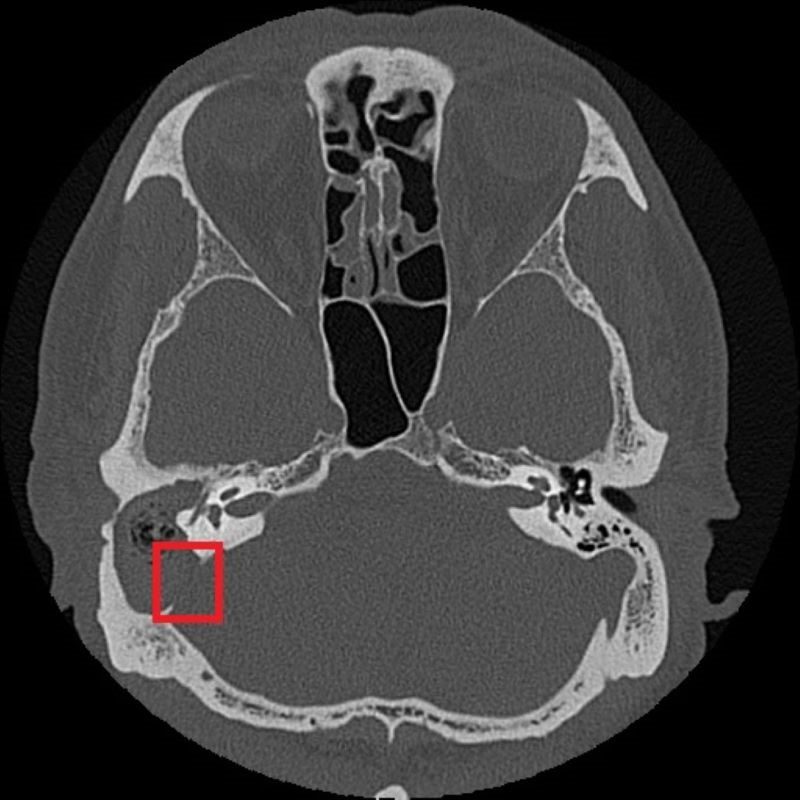

紅框處可見與後顱窩相隔的骨板被膽脂瘤侵蝕。

由於膽脂瘤多發生在中耳或接近顱底的位置,一旦形成,可能影響聽力與神經功能,其分泌物亦容易滋生細菌,導致反覆感染;若未及時治療,可能引發暈眩,甚至因鄰近顱內而造成腦膜炎、腦炎或腦膿瘍。目前,手術切除是膽脂瘤根治的唯一方法,術前需以顳骨電腦斷層檢查評估膽脂瘤範圍及侵蝕程度;手術方式依病灶大小、位置,可能採耳內微創、耳前或耳後切開術,徹底清除膽脂瘤並重建受損結構。急性發炎期則需輔以抗生素控制感染,術後追蹤可降低復發風險,但膽脂瘤若已侵蝕骨質,仍需長期觀察。以張先生為例,雖前後接受過局部藥物、抗生素治療,但考量其慢性中耳炎併發膽脂瘤已破壞聽小骨、乳突及部分顱底骨質,因此需從耳後切開進入外耳道及中耳腔,打開耳後的乳突骨,將病變組織除去後,重建修復骨骼和軟組織缺口。